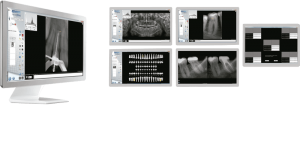

Radiovisiógrafo New Ida

El sistema radiográfico digital New IDA cuenta con un sensor que usa las tecnologías asociadas del CMOS (Complementary Metal-Oxide-Semiconductor), fibra óptica protectora y centelleada. Ese sensor fue fabricado para adquirir la imagen de rayos x digital de alta calidad de la arcada humana y sus estructuras.El proceso de adquisición es realizada posicionado el sensor en la parte interna de la boca atrás de la estructura que se desea realizar el examen.

La estructura debe ser expuesta a una dosis de rayos x usando una fuente externa. Una vez expuesto, el sensor realiza una conversión de los fotones de rayos x en una señal digital y enseguida transfiere para una computadora vía conexión USB (Universal Serial Bus). El software de gestión de imagen dental realiza el interfaz con el sistema New IDA y el usuario, podrá visualizar, mejorar, almacenar, enviar, imprimir entre otras funciones

Es el sensor digital intraoral de DabiAtlante que ofrece imágenes de solución eficiente para obtener un diagnóstico más claro, preciso y avanzado.